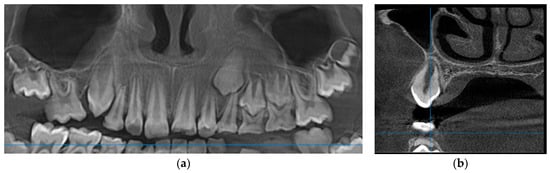

- Allison, J.R.; Garlington, G. The value of cone beam computed tomography in the management of dentigerous cysts—A review and case report. Dent. Update 2017, 44, 182–188. [Google Scholar] [CrossRef] [PubMed][Green Version]

- Erdelyi, R.-A.; Duma, V.-F.; Sinescu, C.; Dobre, G.M.; Bradu, A.; Podoleanu, A. Dental diagnosis and treatment assessments: Between X-rays radiography and optical coherence tomography. Materials 2020, 13, 4825. [Google Scholar] [CrossRef]

- Erdelyi, R.-A.; Duma, V.-F.; Sinescu, C.; Dobre, G.M.; Bradu, A.; Podoleanu, A. Optimization of X-ray investigations in dentistry using optical coherence tomography. Sensors 2021, 21, 4554. [Google Scholar] [CrossRef]

| 3 | 13 y/o | F | Maxilla | 2.3 (left maxillary canine) | yes | 1.73 |